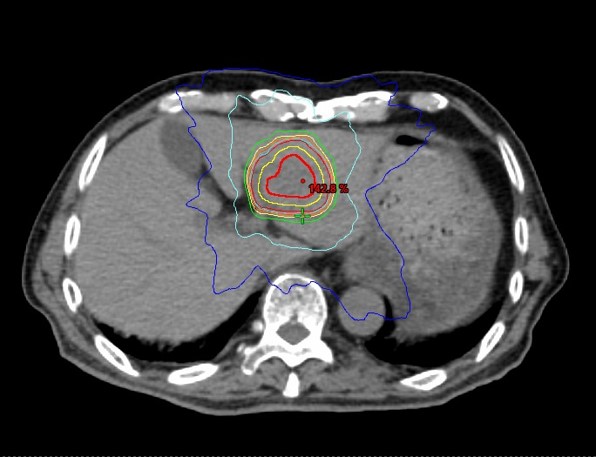

図 肝腫瘍に対する定位放射線治療の線量分布

近年、高精度放射線治療の技術が発達し、定位放射線治療(SBRT)が肝腫瘍に対する治療の新たな選択肢として用いられるようになりました。手術が困難な場合や、他の治療法が適応とならないケースにおいて有望な治療法です。

放射線治療前には、あらかじめ腫瘍の近くに純金製の金属マーカーを留置します。この処置のため事前に1泊2日程度の入院が必要です。

放射線治療を行う際には、治療装置の寝台上でコーンビームCTという画像を撮影し、呼吸に伴う腫瘍の位置変化を4次元的に評価します。これにより、病変に対する正確な線量投与と不要な広範囲への照射の回避が可能となります。

文献によると、局所制御率は80~95%と高い成績が報告されており、今後の治療適応拡大が期待されている治療法です。